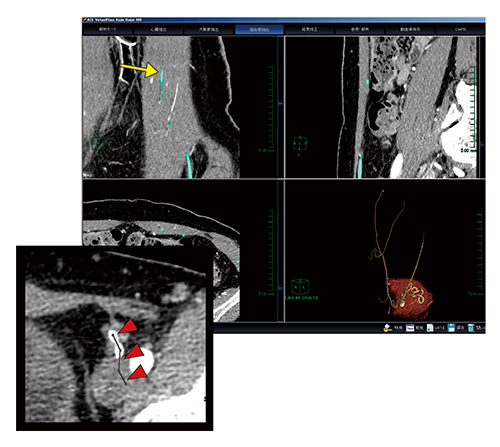

AZE VirtualPlace 雷神での穿通枝の抽出は,以下の手順で行う。まず,画像をCT細血管解析に取り込み,“解析モード”をマニュアルで実行する。次に,“大動脈抽出”では膀胱辺りに仮想点を設定する(図1)。“細血管抽出”は,左右総腸骨動脈から分岐している下腹壁動脈におのおの数点打ち,自動追跡を行う。自動追跡で下腹壁動脈本幹が抽出された後,穿通枝をマニュアルで抽出していく。本ソフトウェアでは各断面が1画面で表示されているため,同定しやすい断面で穿通枝にポイントを設定して抽出し,マスクの反映を行っていく。この方法であれば,皮下レベルの血管まで作成可能である。また,マスク反映した血管はカラー表示されるため,未抽出血管も一目でわかり,見落としなく作成することが可能である(図2,3)。

元画像で同定できるすべての穿通枝を描出した後,3Dレイヤーへ移動し,腹直筋のマスクを作成してマルチレイヤー表示させれば完成である。当院では,動脈の腹直筋内の走行や穿通枝の分岐がわかりやすいことから,MIP表示で行っている(図4)。

図3 穿通枝のマニュアル抽出方法

細血管抽出の画面に戻り,抽出されていない血管をポイントし,マニュアルで抽出,マスクの作成を行う(▶)。この作業を繰り返すことで,すべての穿通枝の描出を可能とする。

術前画像の作成

作成した画像は,形成外科医とともに筋膜から分岐する穿通枝と臍にポイントを描画し,術前画像として役立てられている。臍からの距離と個々の穿通枝との関係を事前に同定しておくことで,術中においても目的とする穿通枝を同定することが可能となる(図5)。